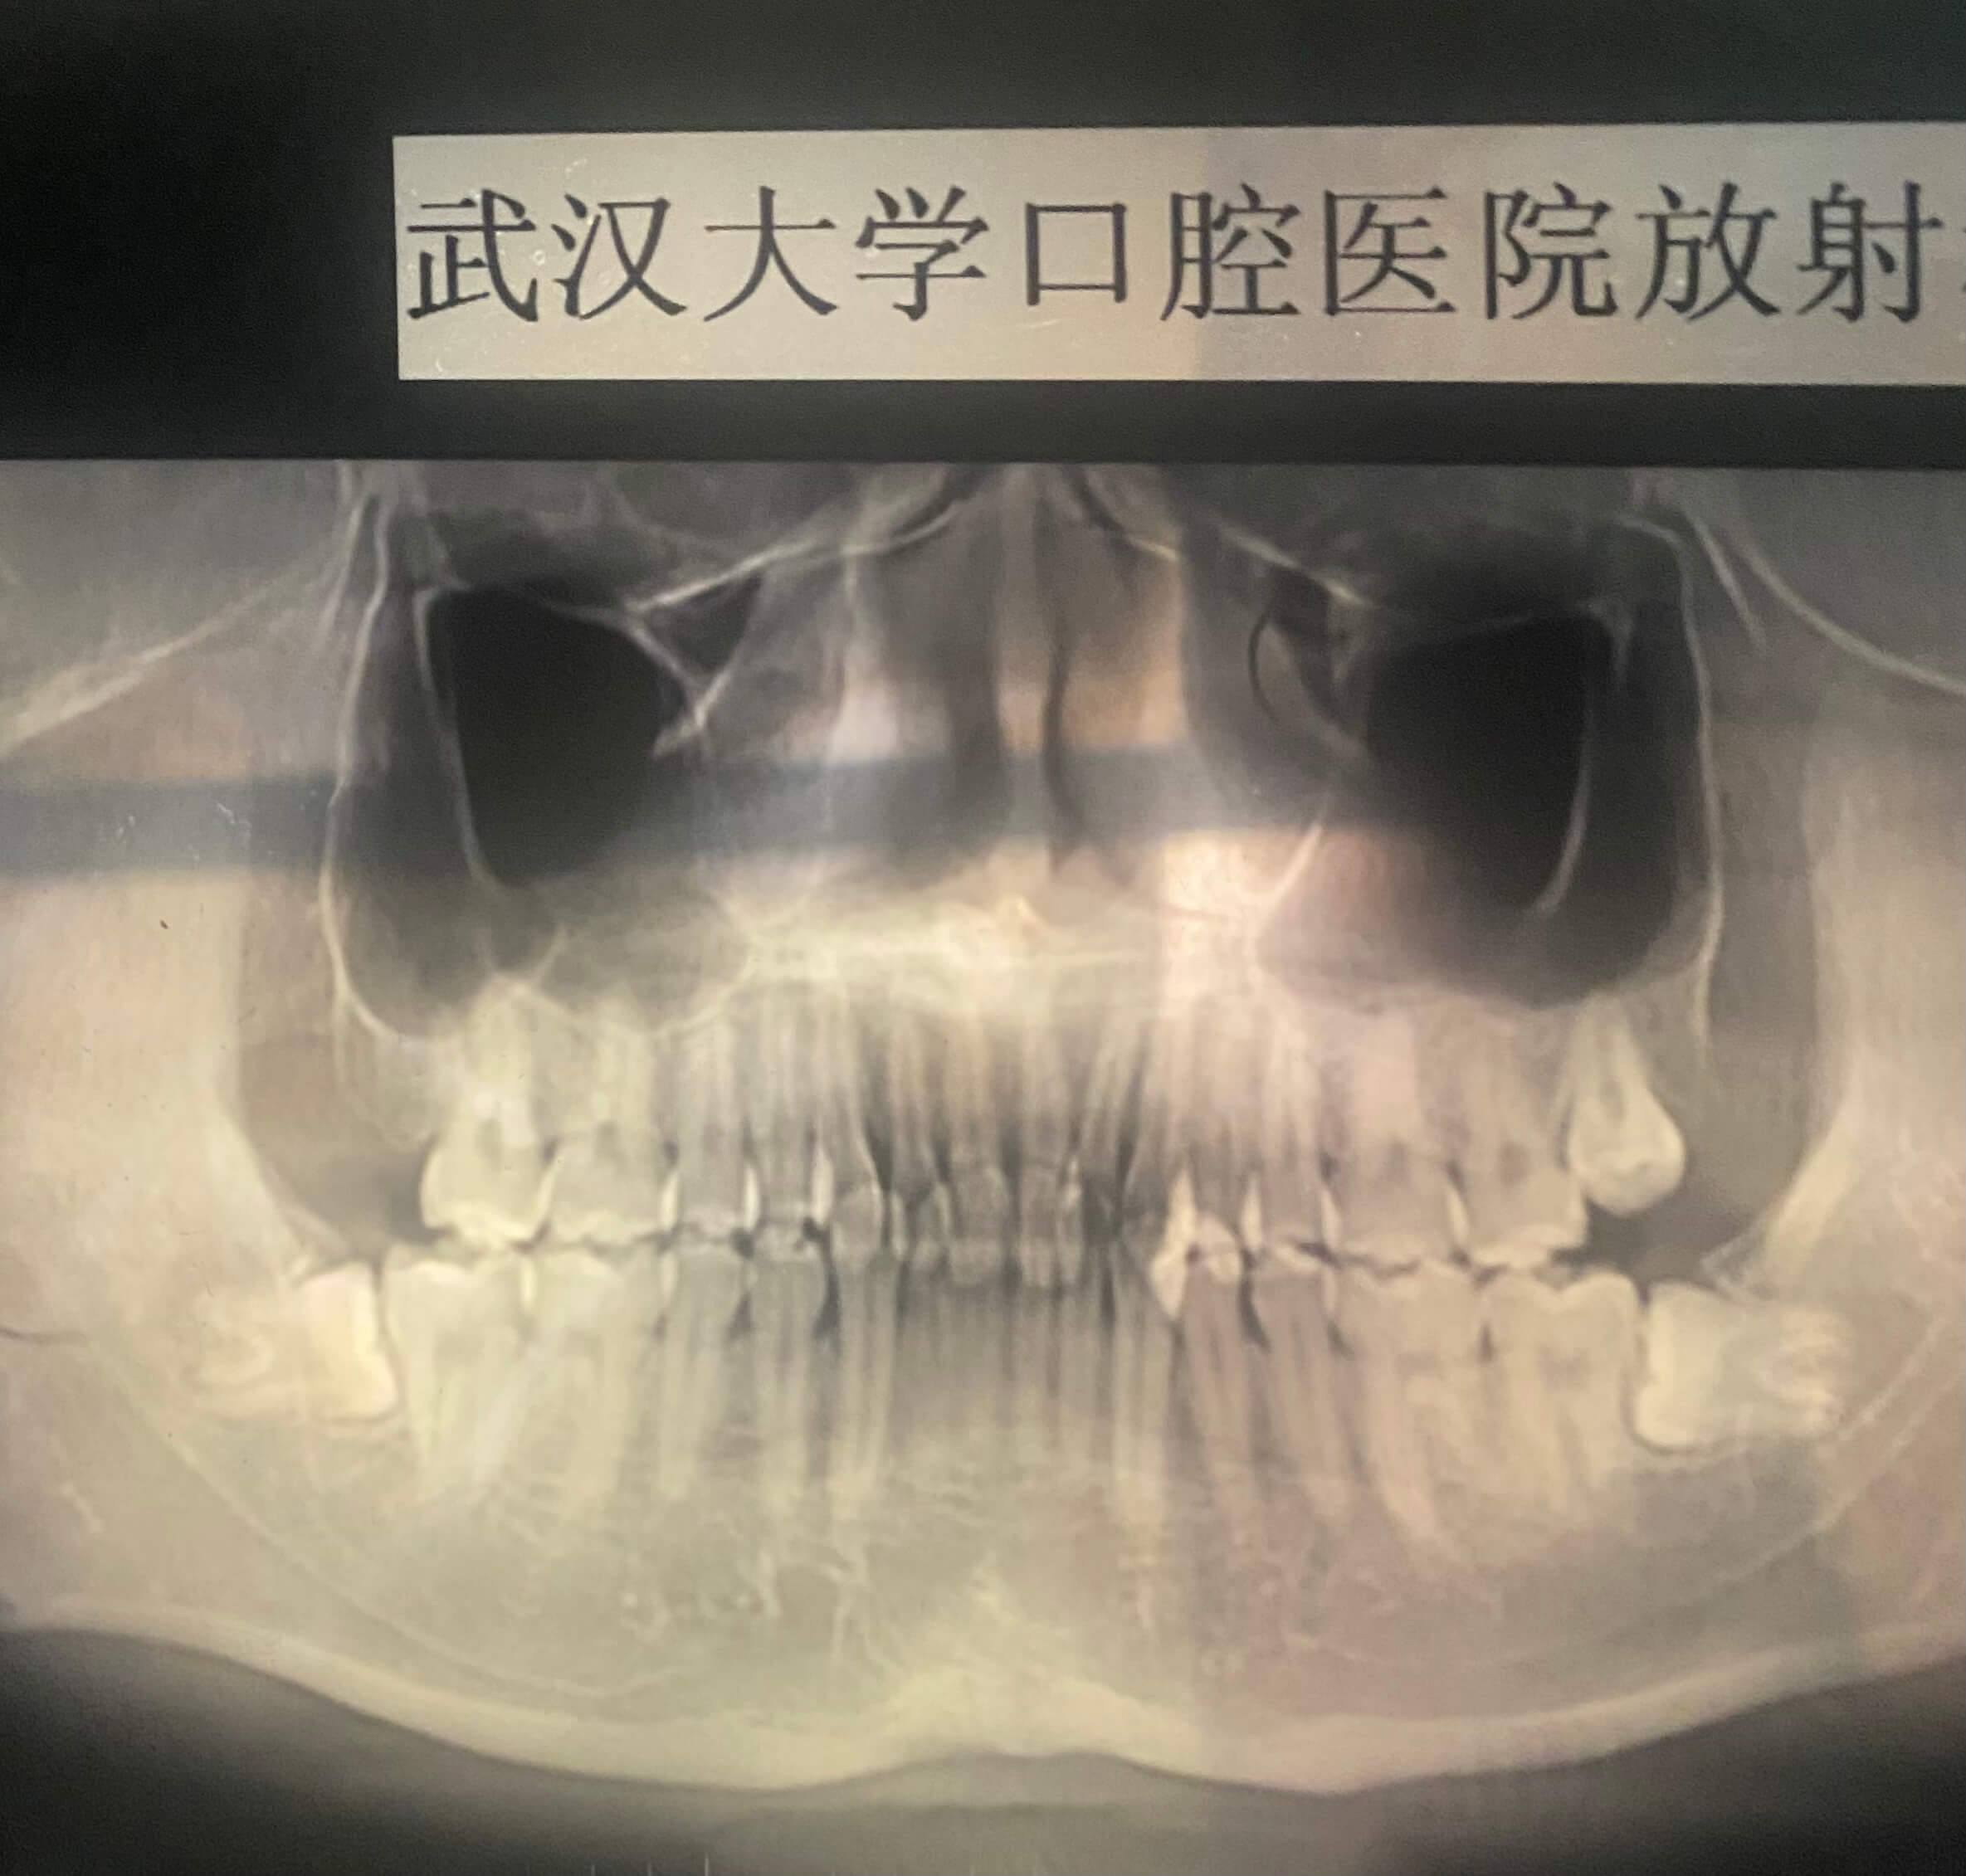

11 月 23 日,星期四下午没课。于是前往武大口腔面诊,签到后排队等了大概十几分钟,就轮到我了,医生简单查看了一下我的牙齿情况,说可以做,金属费用大概在 1.8w ,隐形费用大概在 3w 左右,让我回去和家里人商量一下再过来,我出门和我妈打了个电话,我妈还是挺支持我的,于是直接和医生说做。医生让我去拍片,拍完片子大概就等一周后过来谈方案。

一周后来复诊,医生看了片子说,我有三颗智齿要拔掉,三颗都是那种不太好拔的那种,两颗水平阻生和一颗垂直阻生,三颗牙齿都是长肉里面的,需要去切开牙龈才能看见。

这还是比较简单的,最让人头疼的是根尖腭侧有一倒置多生牙,万万没有想到大门牙后面还有一颗牙,完全长在肉里,看都看不到,要不是这次拍片我还真不会注意到。这颗牙比较复杂,医生说是相当于一个小手术了。

医生通过牙片总结出来的结果是:凸面型,下颌后缩,颏唇沟较深,上下前牙拥挤,前牙闭锁型深覆盖,中线徧左,磨牙远中,TNJ 触诊时双髁突动度不一致。给出的方案是要先去把智齿都拔掉,然后再去上上牙套,因为门牙太内扣了,必须把门牙往外扳回原位,让前牙呈现一个弧度,先调整咬合才可以去上下半口的牙套,还要根据其情况拔正畸牙,先暂时不拔好牙齿。她还说,如果早点去矫正就好了,可以把颏唇沟较深的问题给解决。